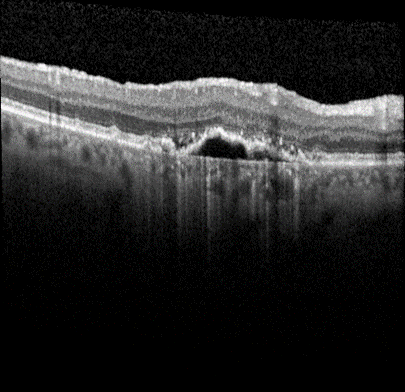

Advanced form of age-related macular degeneration (AMD) is a major health burden that can lead to irreversible vision loss in the elderly population. For early preventative interventions, there is a lack of effective tools to predict the prognosis outcome of advanced AMD because of the similar visual appearance of retinal image scans in the early stage and the variability of prognosis paths among patients. An early characteristic of AMD is drusen, which appears as yellowish deposits under the retina (Figure 1 left). AMD is mainly categorized into two types: Dry AMD (non-neovascular, Figure 1 middle) is represented by drusen deposition, later evolving into confluent areas of regressed drusen and ultimately in the advanced dry stage presenting as loss of vision associated with retinal pigment epithelium (RPE) atrophy (clinically known as geographic atrophy, GA). Wet AMD (neovascular, Figure 1 right) is characterized by the leakage of fluid in the sub-RPE and subretinal spaces caused by neovascularization. The overall objective for this study is to design, develop, and evaluate AMD prognosis prediction models that can detect most relevant images containing AMD biomarkers, manage unevenly spaced sequential optical coherence tomography (OCT) images and predict all advanced AMD forms that can help with the interpretation and explainability of computer-aided prognosis models. Read more

Figure 1: Dursen (left), Dry AMD (middle) and Wet AMD (right)